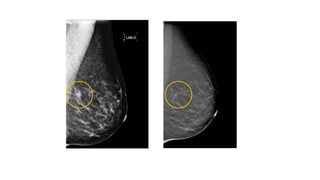

Why Breast Tomosynthesis (3D mammography)?

• Tissue superimposition hides

pathologies in 2D

• Tissue superimposition mimics

3D Improves Visibility by Reducing

Tissue Superimposition

2D Mammogram Tomosynthesis

Better Sensitivity

Fewer Recalls